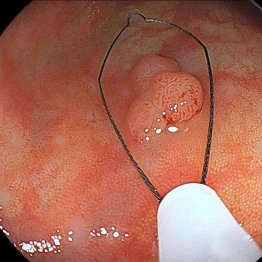

杉浦さんは2020年1月と21年6月にも大腸ポリープを2個ずつ切除し、この5年間で3度も切除したことになる。いずれも大腸内視鏡検査の際、切除したものだ。